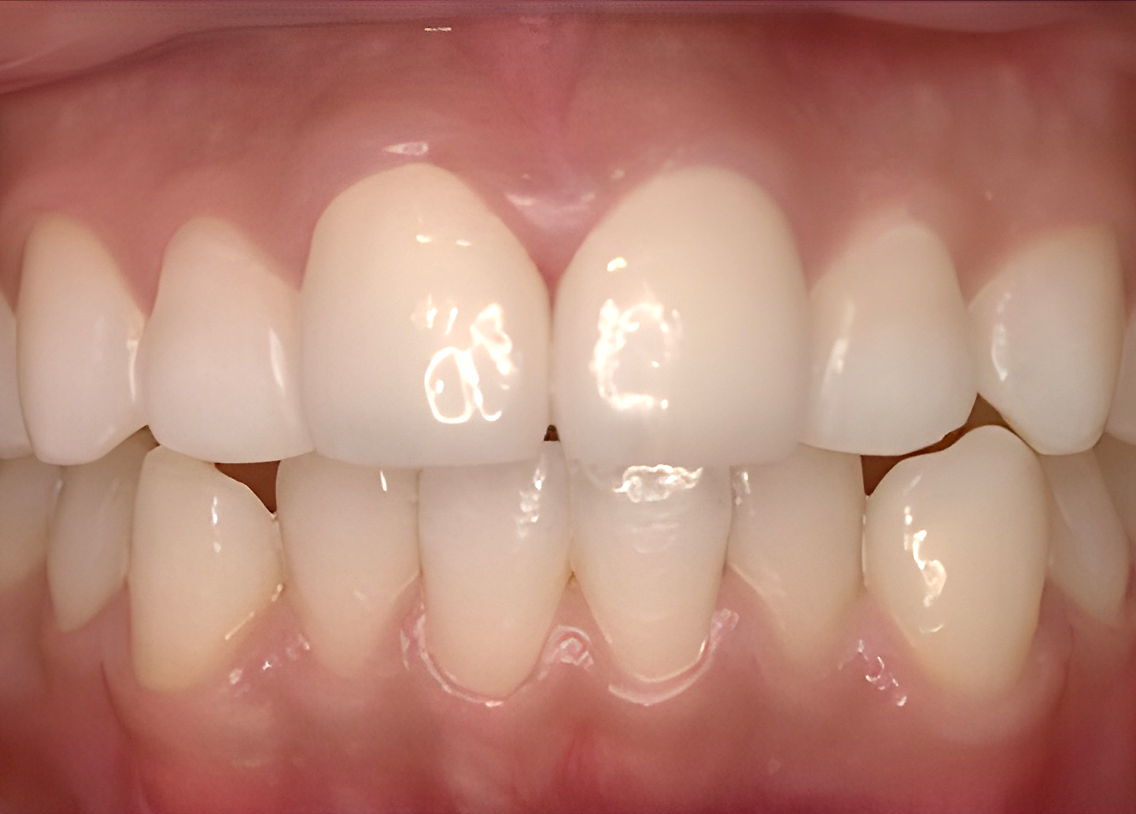

Before

after